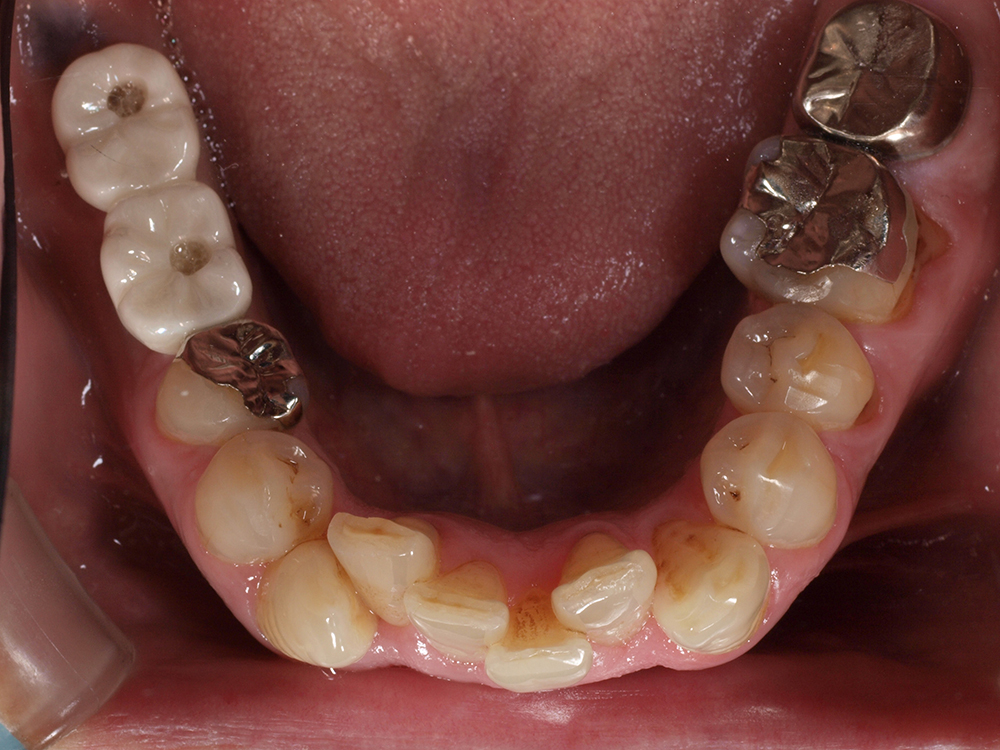

53歳 男性

- 主訴

- 全然噛めない。上の歯が取れてきた

- 処置内容

- 上顎:8本 下顎:2本

- 治療費用

- 上顎:約320万円(税込)、下顎:約160万円(税込)

- 治療期間

-

上顎:1年(仮歯まで8か月)

下顎:8か月(仮歯まで5か月)

- リスク

- 上部構造物、仮歯の破折、術後の腫れ(3日)、人工歯根脱落リスクがあります